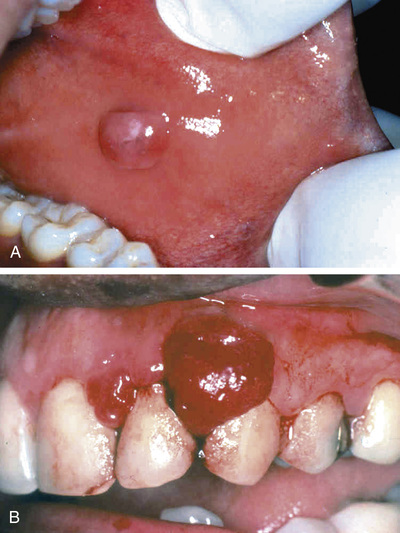

Fibromas are submucosal nodular fibrous tissue masses that are formed when chronic irritation results in reactive connective tissue hyperplasia (Fig. 15.2A). They occur most often on the buccal mucosa along the bite line. Treatment is complete surgical excision and removal of the source of irritation.

Pyogenic granuloma (Fig. 15.2B) is an inflammatory lesion typically found on the gingiva of children, young adults, and pregnant women (pregnancy tumor). These lesions are richly vascular and typically ulcerated, which gives them a red to purple color. In some cases, growth can be rapid and raise fear of a malignant neoplasm. However, histologic examination demonstrates a proliferation of immature vessels similar to that seen in granulation tissue. Pyogenic granulomas may regress, mature into dense fibrous masses, or develop into a peripheral ossifying fibroma. Complete surgical excision is definitive treatment.